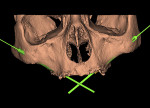

The digital imaging and communications in medicine (DICOM) data from the 3D scan first is exported from the imaging device and then imported into the implant planning software. Through the use of the diagnostic tools within the software, the entire maxillary anatomy is studied for any anatomical variations, density, topography of the maxillary sinus, and potential pathology. Consequently, the alveolar bone and zygomatic bone are evaluated for receptor sites that may be most suitable for insertion of the zygomatic implants. The simulation for the implant placement is used to define the entrance point, trajectory path (implant path), and exit point of the implants (Figure 1 and Figure 2).

As with conventional guided implant planning, there is not one view that contains enough information for definitive planning. Therefore, clinicians must utilize both the 3D and 2D views in the various spatial planes, depending on the software application used. These include coronal, axial, panoramic, cross-sectional, and sagittal oblique.